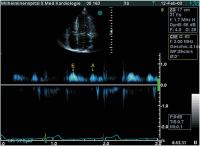

Transmitrale CW-Dopplerregistrierung

Abbildung 2: Transmitrale CW-Dopplerregistrierung; jeder LA-Kontraktion folgt eine diastolische Regurgitation, max. Gradient über 7 mmHg, allmähliche Geschwindigkeitsabnahme durch den druckausgleichenden Pulmonalveneneinstrom, abrupte Unterbrechung des dMR-Signals durch die einsetzende Systole (dMR = diastolische Mitralregurgitation, E = frühdiastolische Füllung, A = A-Welle durch atriale Kontraktion)